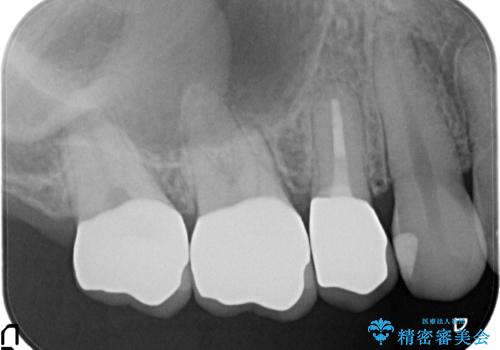

- 他院にて右上5番目の歯の根管治療を行っていたが、痛みが引かないため当院にいらっしゃった方の症例です。

右上5は再根管治療を行い症状の緩解を確認後、オールセラミッククラウンによる補綴を行いました。

右上6、7番目の歯もしみるとのことだったので古い樹脂及び虫歯を除去後、オールセラミッククラウンによる補綴を行いました。

- オールセラミッククラウン(スタンダード)…¥100,000×3、ファイバーコア…¥20,000×1、仮歯…¥10,000×3費用は治療当時の料金となります